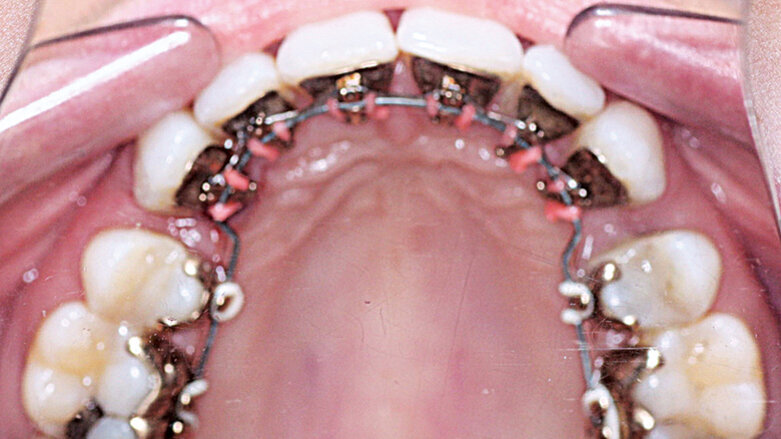

Po naskenování modelů byl návrh léčebného plánu odeslán ke zhotovení zámků a drátěných oblouků. Protože byla plánována extrakce zubů 14, 24, 34 a 44, byly na zámky 17, 27, 37 a 47 požadovány háčky k usnadnění zavádění el. řetízků používaných ve fázi uzavírání mezer.

Byly zvoleny tyto drátěné oblouky pro jednotlivé fáze léčby:

Nivelizace NiTi .014, NiTi .016 × .022

Pro zvýšení torze před fází uzávěru mezer byl použit NiTi .017 × .025.

Pro konsolidaci zbytkových mezer byl použit ocelový oblouk .017 × .022.

Závěrečná fáze léčby proběhla na oblouku TMA .175 × .175.